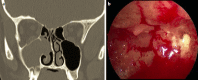

Endonasal endoscopic sinus surgery is the standard procedure for surgery of most paranasal sinus diseases. Appropriate frame conditions provided, the respective procedures are safe and successful. These prerequisites encompass appropriate technical equipment, anatomical oriented surgical technique, proper patient selection, and individually adapted extent of surgery. The range of endonasal sinus operations has dramatically increased during the last 20 years and reaches from partial uncinectomy to pansinus surgery with extended surgery of the frontal (Draf type III), maxillary (grade 3-4, medial maxillectomy, prelacrimal approach) and sphenoid sinus. In addition there are operations outside and beyond the paranasal sinuses. The development of surgical technique is still constantly evolving. This article gives a comprehensive review on the most recent state of the art in endoscopic sinus surgery according to the literature with the following aspects: principles and fundamentals, surgical techniques, indications, outcome, postoperative care, nasal packing and stents, technical equipment.